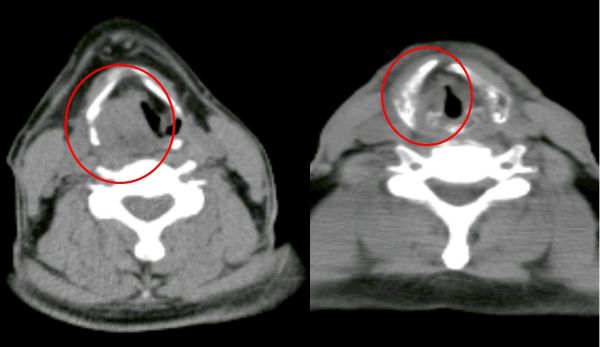

經耳鼻喉科醫師安排內視鏡檢查,於下咽部位發現可疑病灶,切片檢查後確診為下咽癌,並透過電腦斷層等影像檢查綜合評估,判定為第三期。突如其來的診斷結果,讓病人與家屬感到憂心。